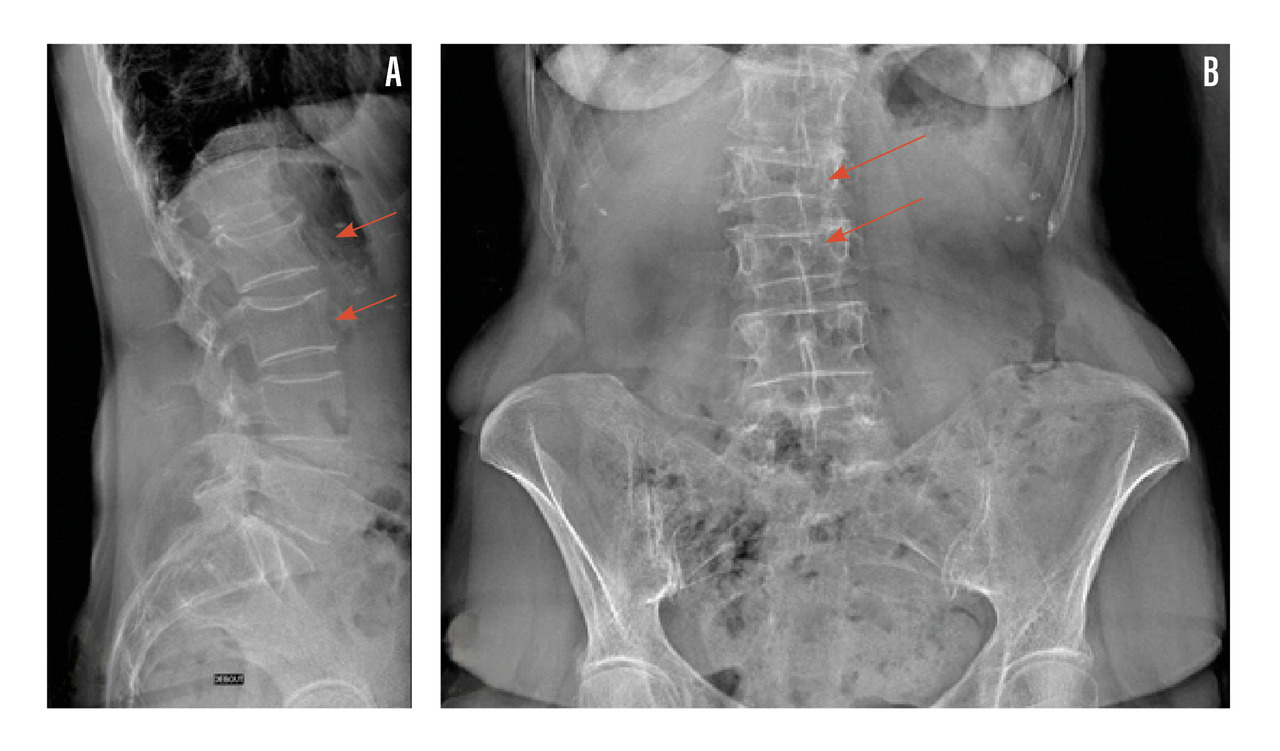

Ostéodensitométrie osseuse, l’examen de référence

La DMO (ou ostéodensitométrie osseuse) constitue l’examen de référence pour évaluer la densité minérale osseuse. Elle repose sur une technique d’absorptiométrie biphotonique à rayons X (DXA). Il s’agit d’une méthode juste (exactitude de la mesure), reproductible (dans le suivi) et inoffensive (irradiation minime).

Modalités de mesure

La mesure se fait habituellement sur deux sites, dont la proportion en os cortical et trabéculaire varie, à savoir au niveau du rachis lombaire (riche en os trabéculaire) et de la hanche (riche en os cortical) [fig. 2]. En l’absence de mesure possible sur ces sites (en raison de lésion arthrosique trop importante, prothèse, arthrodèse), la mesure peut se faire au poignet.